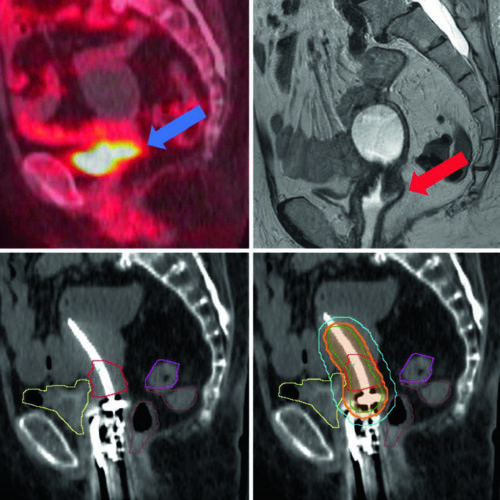

Delineamento de Volumes

Guias práticos de delineamento de volumes-alvo e órgãos de risco por sítio anatômico na radioterapia.